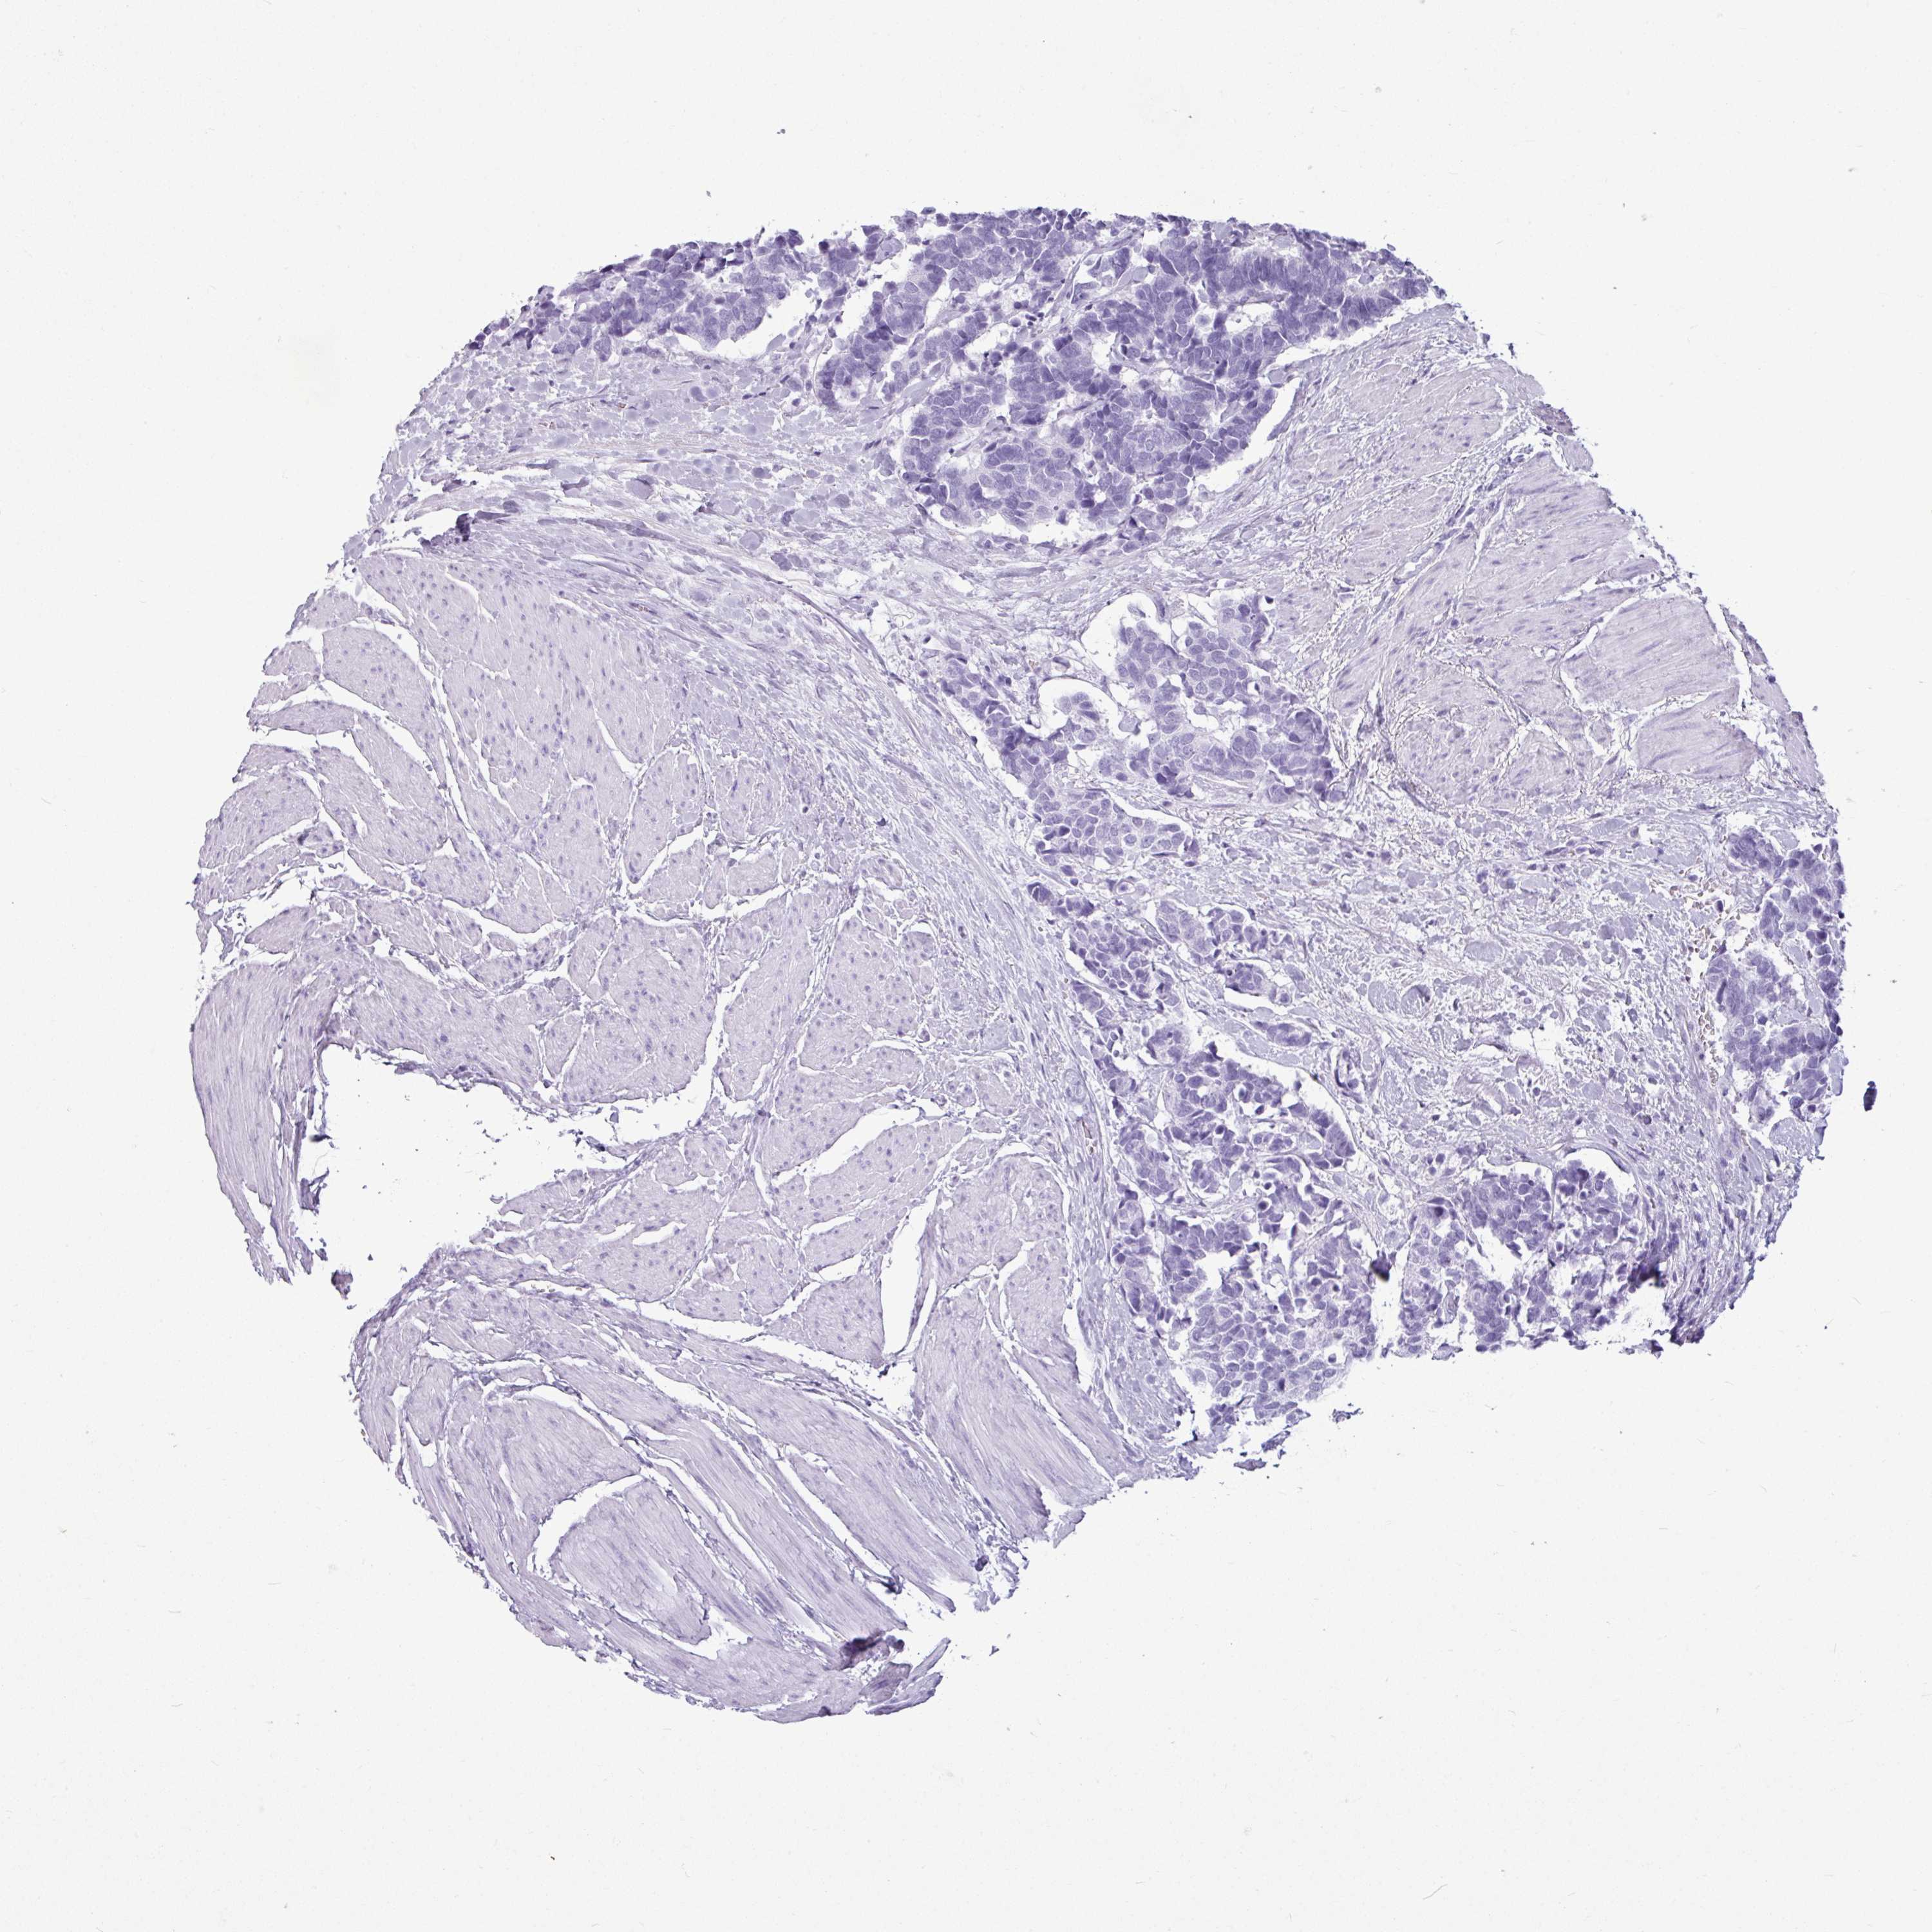

AMY1C